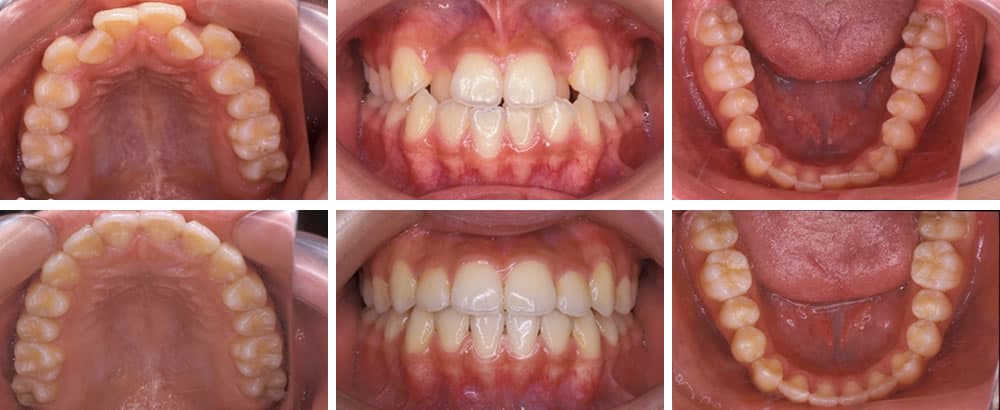

叢生(八重歯など)

叢生は歯が様々な向きに生え、ばらばらな状態の歯並びです。歯が重なった部分のケアが難しいため、虫歯や歯周病リスクが高くなります。また、見た目も悪くコンプレックスに感じる方も少なくありません。